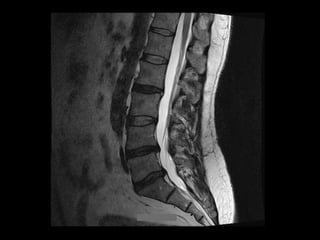

DISCECTOMY FOR DISCHERNIATION Outcome •  Day  Surgery  procedure   •  back  to  sedentary  duHes  in  3  weeks   •  back  to  sport  in  6  weeks   •  good  or  excellent  result  in  90-­‐95%